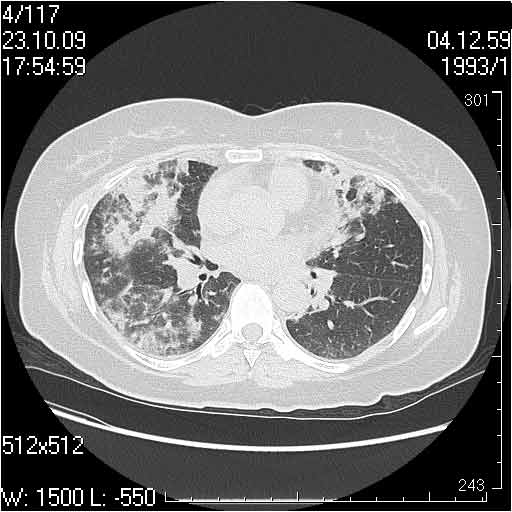

Случай №1

Женщина 50 лет.

Случай 1: изменения характерны для интерстициальной пневмонии (IIP/UIP idiopathic interstitial pneumonia/usual interstitial pneumonia); говорить о конкретной форме без открытой биопсии затруднительно.